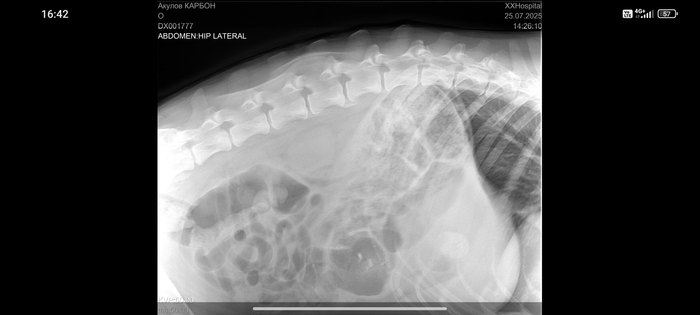

Немецкая овчарка 7лет. Отказали задние лапы

За 5 дней у собаки отказали задние лапы .

Сделали рентген и анализ крови.

Заключение - проблемы в позвоночнике.

Здесь правда Карбон по моложе.